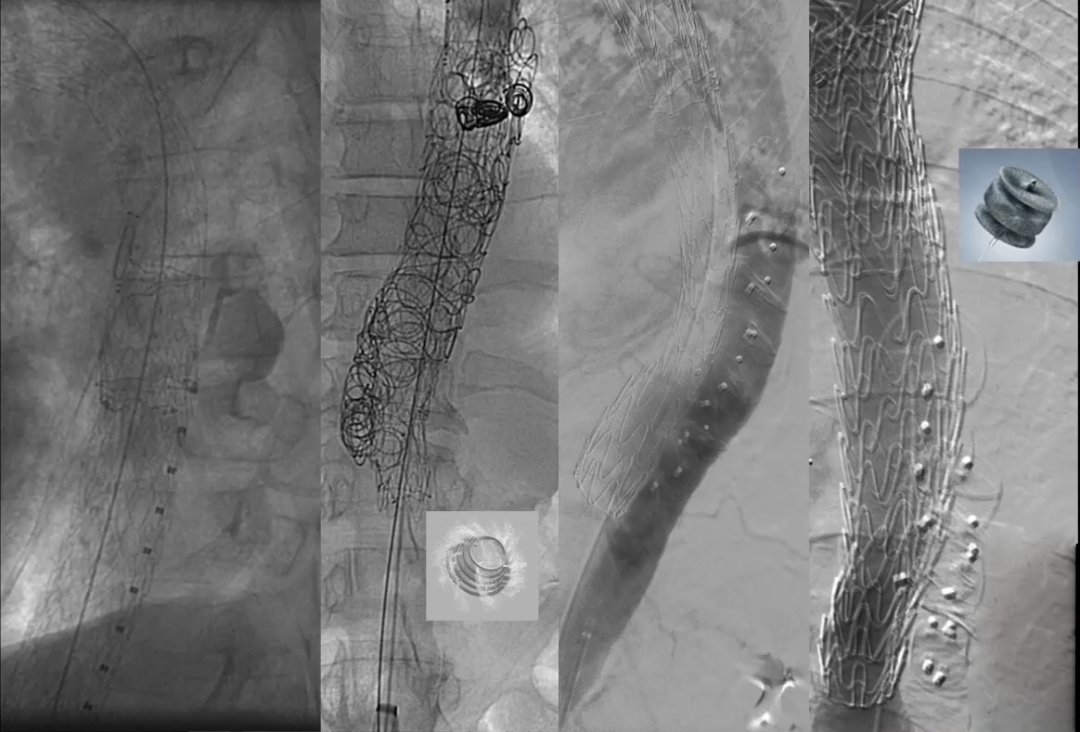

关于诱发假腔内血栓形成共有裸支架(STABILIZE)技术、Knickerbocker技术、假腔栓塞(弹簧圈与血管塞)、Candy-plug这四个技术策略可供参考,接下来我们来进行具体分析。

裸支架,即STABILIZE技术

裸支架最常用于急性夹层,特别是复杂夹层和灌注不良的病例,但是需要注意的是,裸支架一般需要利用球囊,以便更好地支架贴壁和消除假腔。

在下图中可以看出,STABILIZE技术应用在慢性夹层中,保护了肾动脉。

根据下图中的操作细节和结果可以得到的信息为:从出现症状到STABILIZE手术的间隔时间是9个月,可以看到使用球囊对覆膜支架下方的裸支架进行后扩张,改善贴壁并获得更好的定位。

根据下图数据,可以看到STABILIZE技术一个显著的并发症,也是我们必须要注意的地方:在球囊扩张过程中(不能在大于42毫米的远端动脉瘤上进行),会出现假腔血栓远端迁移。可能是因为影响了部分附壁血栓,并使其向远端移动。

Knickerbocker技术

Knickerbocker技术的主要优点是在于它不需要必须进入假腔或者添加更多材料。其概念是使用顺应性球囊,对位于真腔的覆膜大支架的中间部分尽可能进行扩张,有控制地使夹层内膜片破裂,支架中部膨胀至假腔,真腔压迫假腔, 使假腔缩窄。目的是减少假腔逆向返血,促进血栓化。

另一个例子是,在假腔内送入弹簧圈、血管塞甚至打胶栓塞,以便诱发阻塞或血栓形成,如下图所示。

Candy-plug技术

在进入假腔后,可以选择送入Candy-plug,而不是将假腔内填入“腔内垃圾”。该技术最早是由科贝尔医生及同事提出。

Candy-plug如下图所示,是一种特制的血管塞,将袖套(cuff)进行改造,然后用血管塞塞住进行输送,并封闭血管塞的金属部分,这种材料是可以商业化生产的。

可以看到下图中有一个COOK的产品,这种产品在欧洲上市,但是在美国并没有。Candy-plug内部的尺寸比假腔的平均直径大10%~30%,在腹腔干上方1cm处与真腔内的支架平行放置,随后将假腔封堵住。